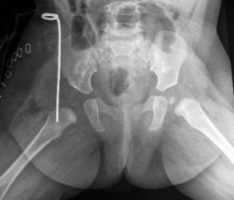

Рентгенограммы больной Т., 10 месяцев. Диагноз: врожденный вывих бедра справа.

2. Открытое вправление бедра в сочетании с транспозицией вертлужной впадины (подвздошной остеотомией таза)

Применяется у детей старше 1 года в тех ситуациях, когда врожденный вывих бедра сочетается с выраженным недоразвитием вертлужной впадины.

Разработанная нами методика подвздошной остеотомии не требует использования трансплантата. То есть, при фиксации фрагментов остеотомии тазовой кости нет необходимости в использовании чужеродных тканей или заборе собственного костного трансплантата.